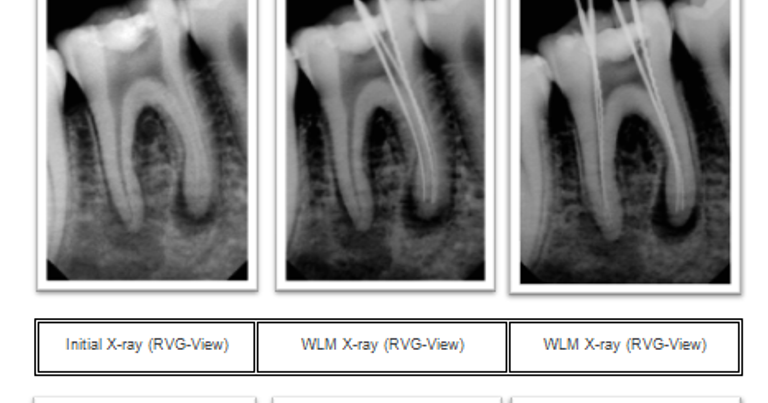

Mandibular First Molar With A Radix Entomolaris An Endodontic

Pdf Mandibular First Molar With A Radix Entomolaris An

Dental Health Endodontic Management Of Mandibular First Molar